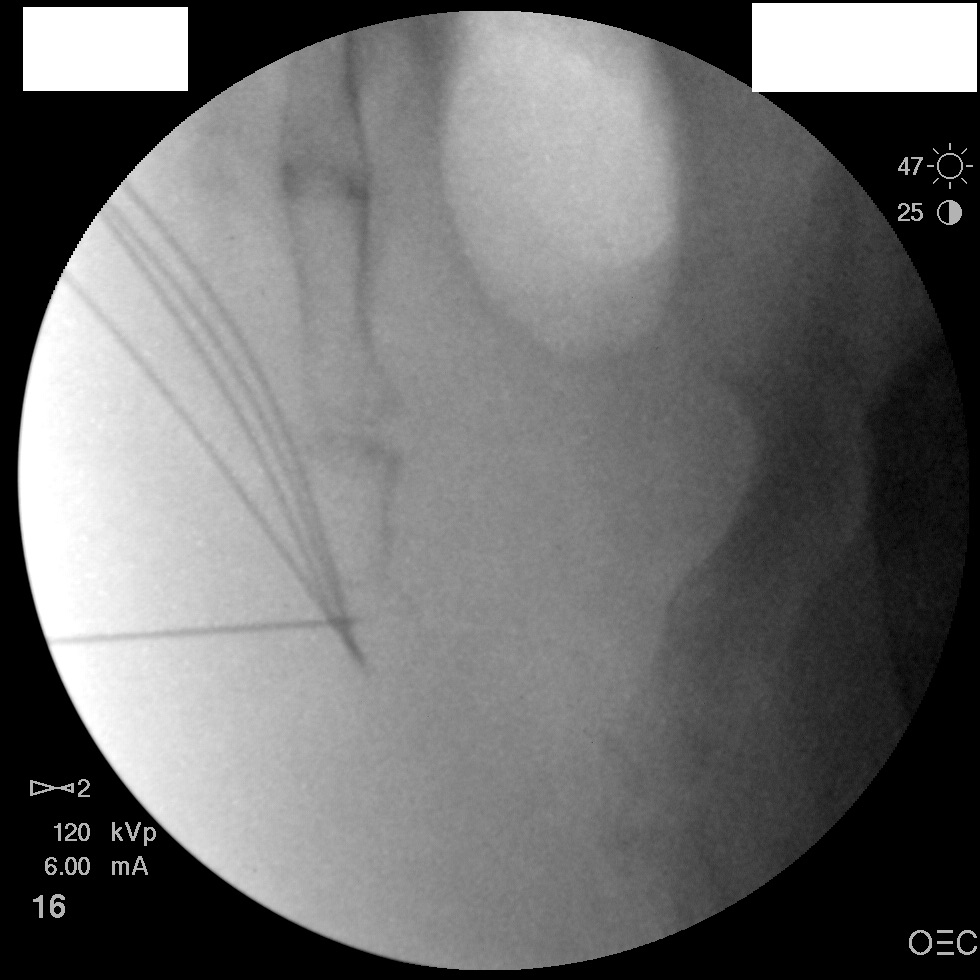

I have a patient with several months of coccyx pain. Worse with sitting, TTP over coccyx. Otherwise normal exam. No trauma, but she has an anteriorly displaced coccyx. Failed NSAIDs and no one around me does good pelvic floor PT. I scheduled her for ganglion impar injection, but her insurance won't pay for it. They wouldn't even let me to a peer-to-peer... they just straight up said they won't cover it. Any other treatment options? I don't want to send her to a surgeon. Thanks.